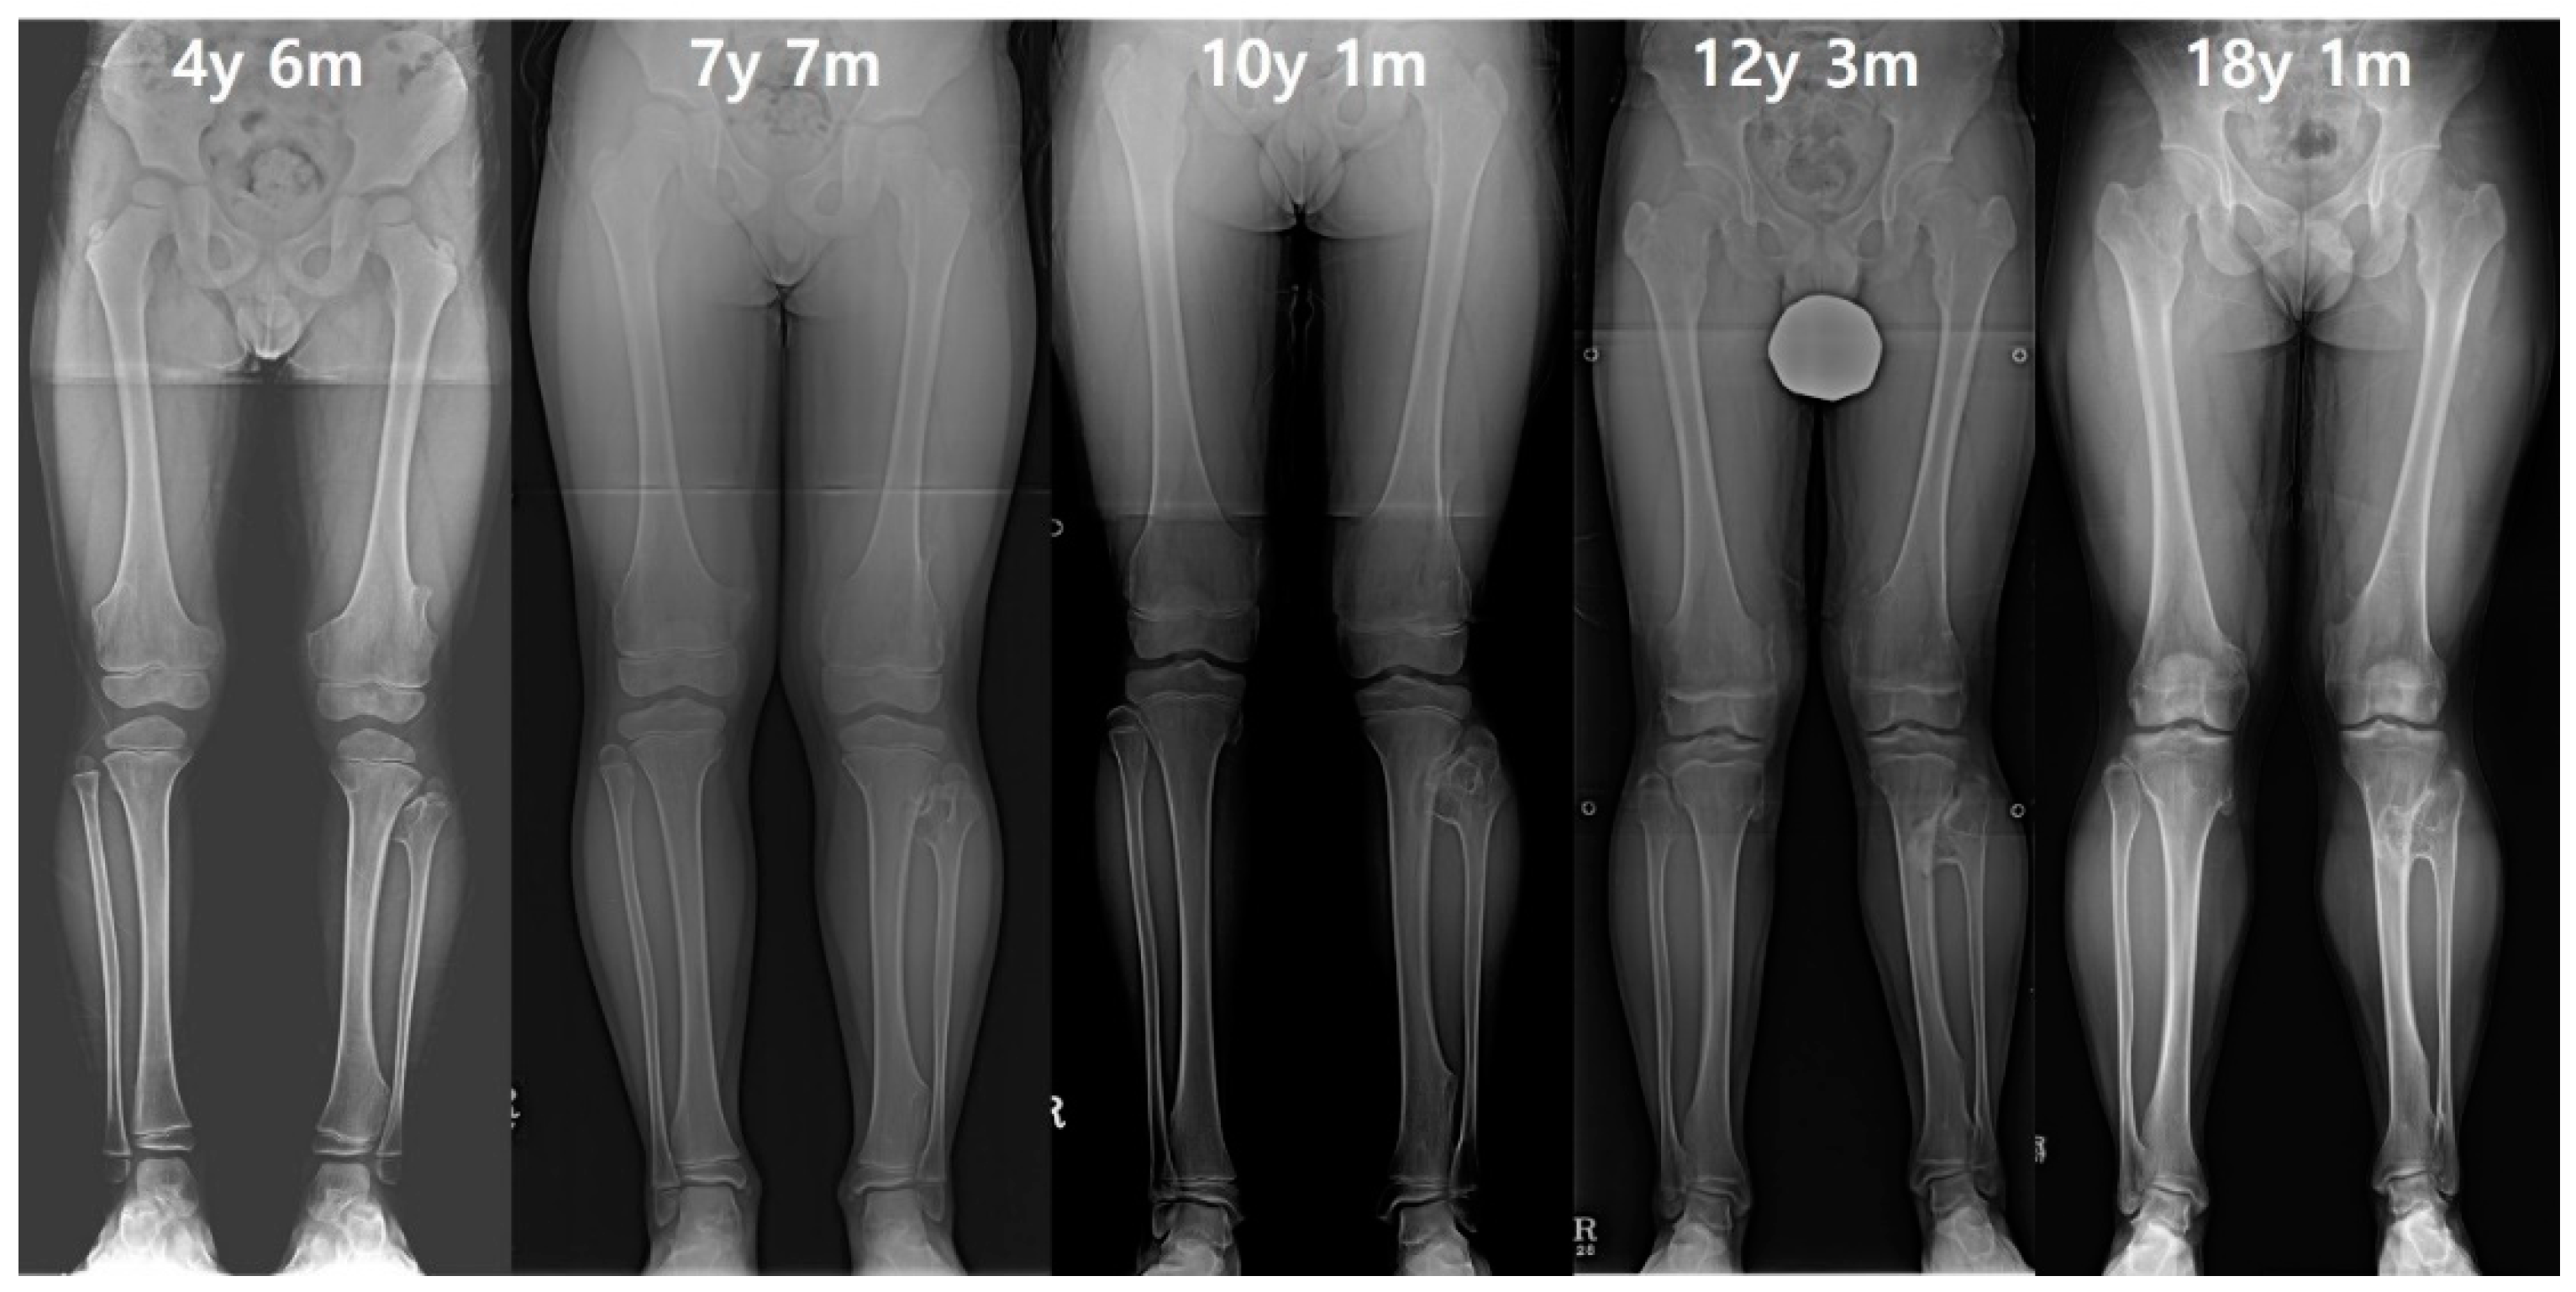

Figure 5. A male patient had prominent exostosis on the left proximal fibula and an increased gap of the proximal tibia and fibula at initial evaluation. Although the right lower extremity initially maintained a normal tibiofibular relationship, after the growth was completed, the right ankle joint developed valgus deformity to be equivalent to the left ankle. Finally, the leg length discrepancy was approximately 12 mm due to the 10 mm shortened length of the left tibia.